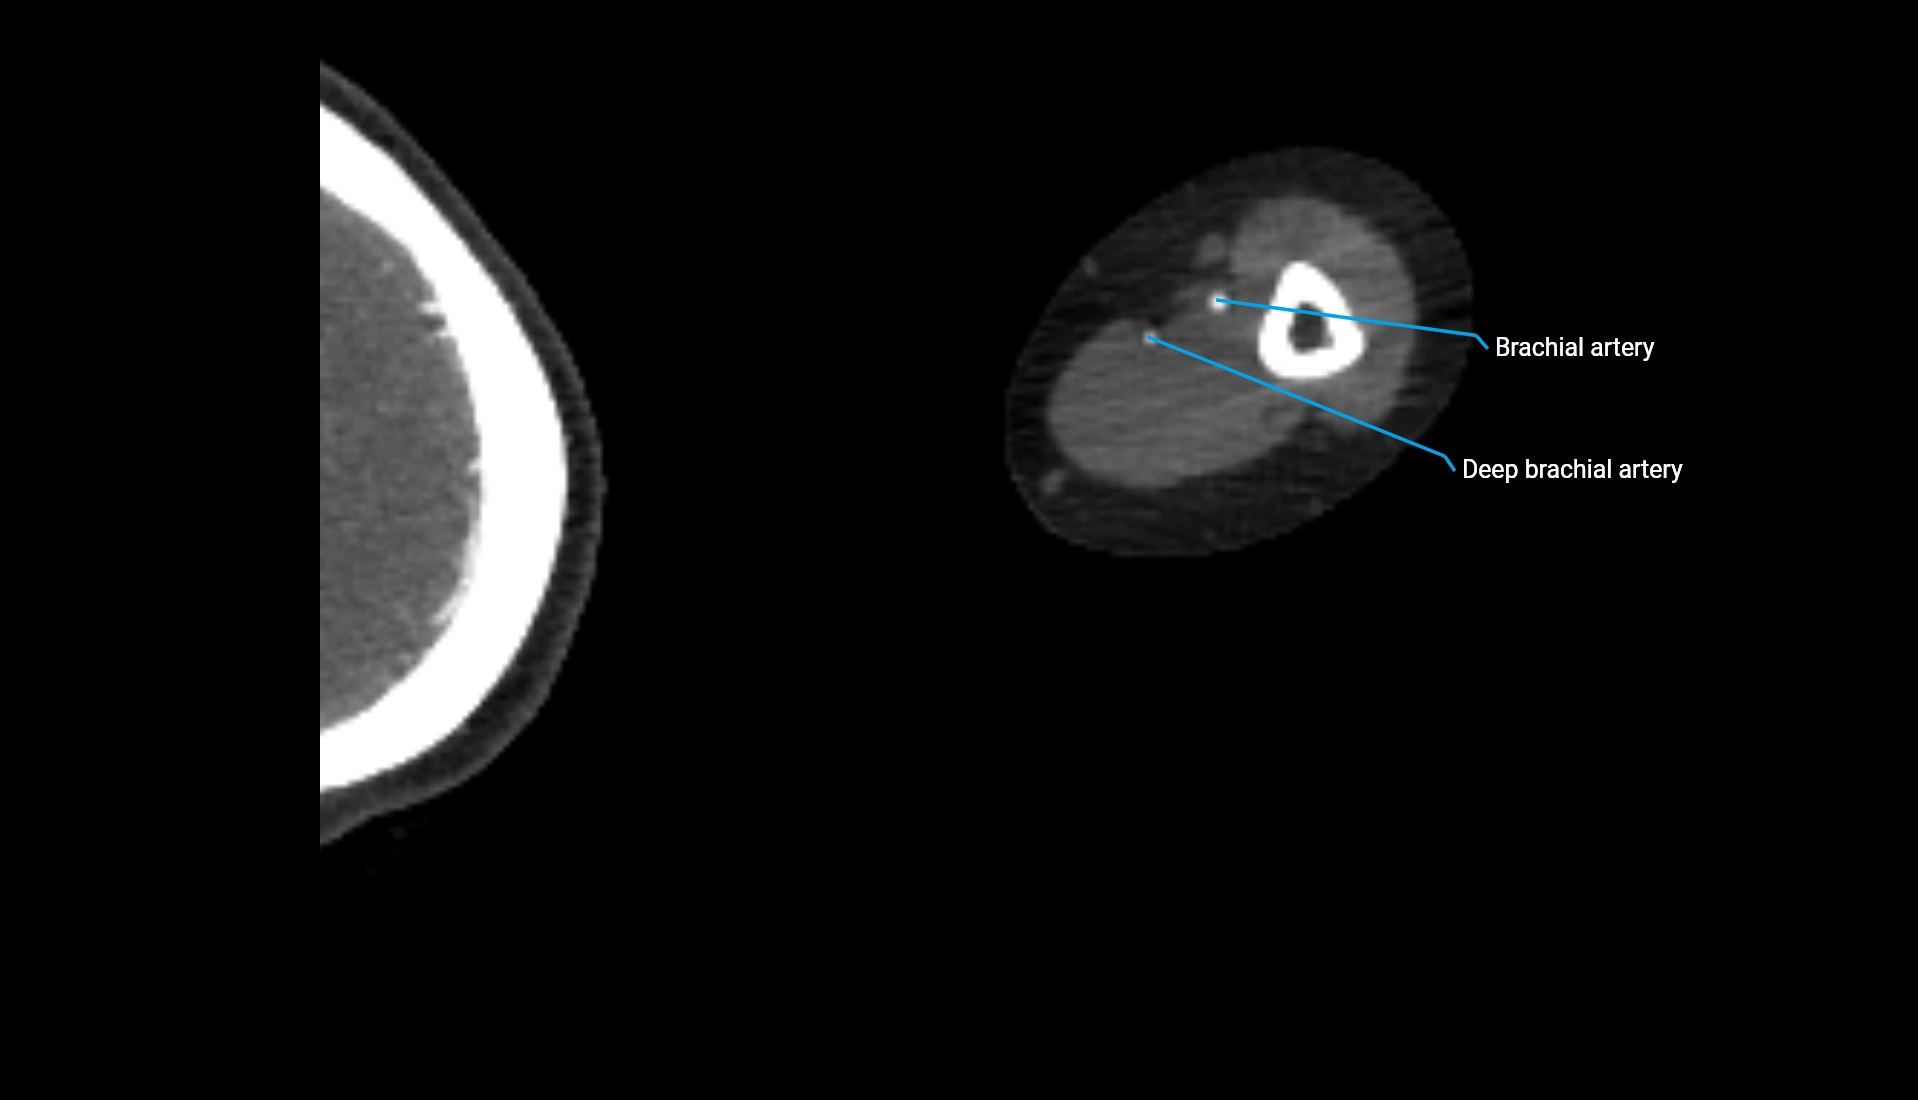

CT Appearance

Non-Contrast CT:

• Cortex: High-density, sharply defined

• Subchondral bone: Dense cancellous matrix

• Articular surface: Smooth concave contour articulating with the capitellum

• Excellent for evaluating bone integrity, alignment, and subtle fractures

Post-Contrast CT:

• Bone: No enhancement

• Joint capsule and synovium: Mild enhancement outlining the joint

• Improves contrast between soft tissues and bony margins

• Useful in detecting subtle joint abnormalities or postoperative changes